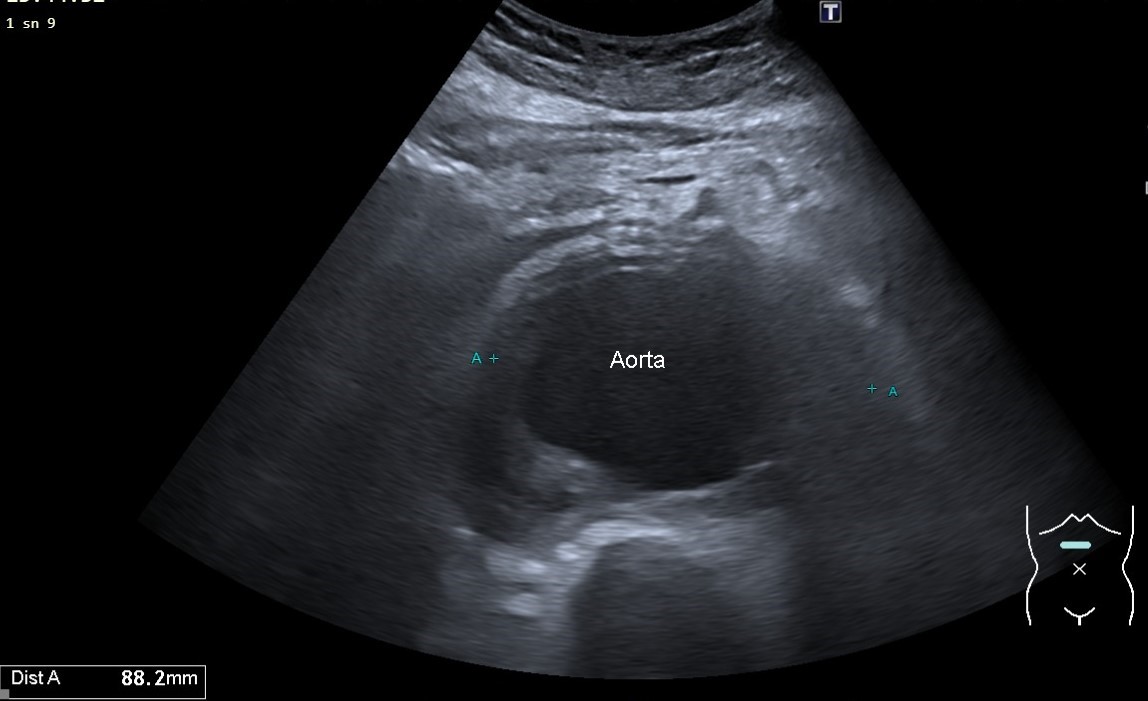

Fig. 6. A transverse ultrasound image of an 83-year-old female with a juxtarenal leaking abdominal aortic aneurysm accompanied by a retroperitoneal hematoma.